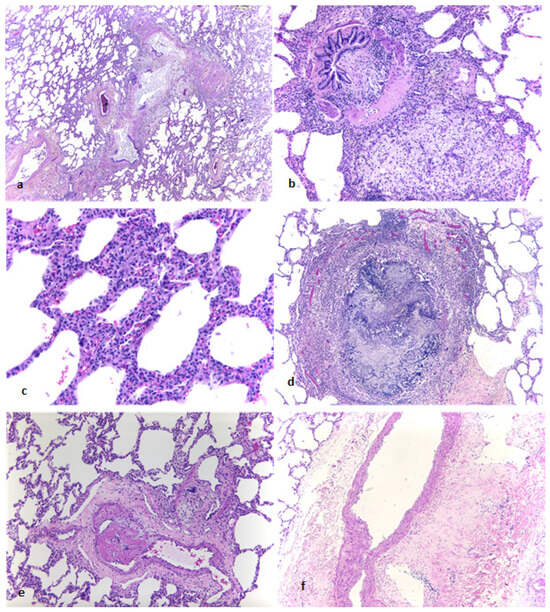

Background: Castleman’s disease (CD), also known as angiofollicular lymph node hyperplasia, describes a rare group of diseases manifesting with enlarged lymph nodes and various inflammatory symptoms. The association between Castleman’s disease, paraneoplastic pemphigus and bronchiolitis obliterans has been described in the literature and

Background: Castleman’s disease (CD), also known as angiofollicular lymph node hyperplasia, describes a rare group of diseases manifesting with enlarged lymph nodes and various inflammatory symptoms. The association between Castleman’s disease, paraneoplastic pemphigus and bronchiolitis obliterans has been described in the literature and is depicted thoroughly in this case. Case Presentation: We present a case of severe bronchiolitis obliterans developing in a 17-year-old female with paraneoplastic pemphigus and unicentric Castleman’s disease. Conclusion: Surgical resection of unicentric Castleman’s disease remains the treatment of choice due to its efficacy in preventing the recurrence of associated morbidity caused by bronchiolitis obliterans and paraneoplastic pemphigus.

Figure 1